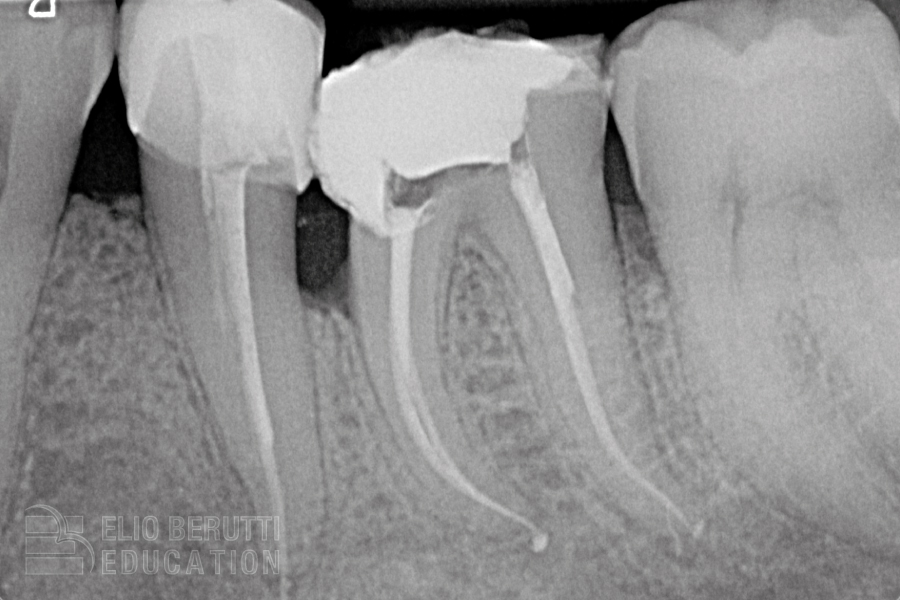

Obiettivo del trattamento endodontico è recuperare un elemento dentale colpito da una patologia irreversibile della polpa. H. Schilder nel 1974 ha rivoluzionato l’endodonzia introducendo gli obiettivi, ancora oggi validi, per ottenere una terapia di successo: detersione 3D ed otturazione 3D del sistema dei canali radicolari raggiungibile mediante una sagomatura che deve essere centrifuga al canale originario.

Tre sono i parametri da seguire per realizzare una sagomatura troncoconica corretta: lunghezza di lavoro, l’ampiezza del forame apicale e la conicità finale della sagomatura. Vorrei a questo punto sottolineare che il nostro obiettivo è la detersione 3D e l’otturazione 3D necessari per eliminare l’infezione canalare. La sagomatura del canale è quindi solo un mezzo per ottenere il risultato. Deve essere pertanto più conservativa possibile garantendo però il nostro obiettivo primario cioè l’eliminazione dei batteri dal sistema dei canali radicolari.

La maggioranza dei canali (più del 90%) sono inizialmente sondabili con una lima 10 (0.010 mm) in questi casi la letteratura dimostra che è sufficiente raggiungere il forame apicale con uno strumento endodontico con un punta 25 o 30 (0,025, 0,030 mm) al fine di raggiungere un buon flusso degli irriganti sino al forame apicale. Allargare ulteriormente il forame è quindi ininfluente ai fini della detersione e pericoloso in termini meccanici (L.G. Coldero 2002, A. Khademi 2006, F. Paqué 2009, C. Boutsioukis 2010, A. El Ayouti 2011, A. Aminoshariae 2015, G. Plotino 2019, O.Y.S. Lee 2019).

⁃ una conicità bassa della sagomatura garantisce il mantenimento dell’anatomia originaria e la resistenza meccanica dell’elemento dentale,